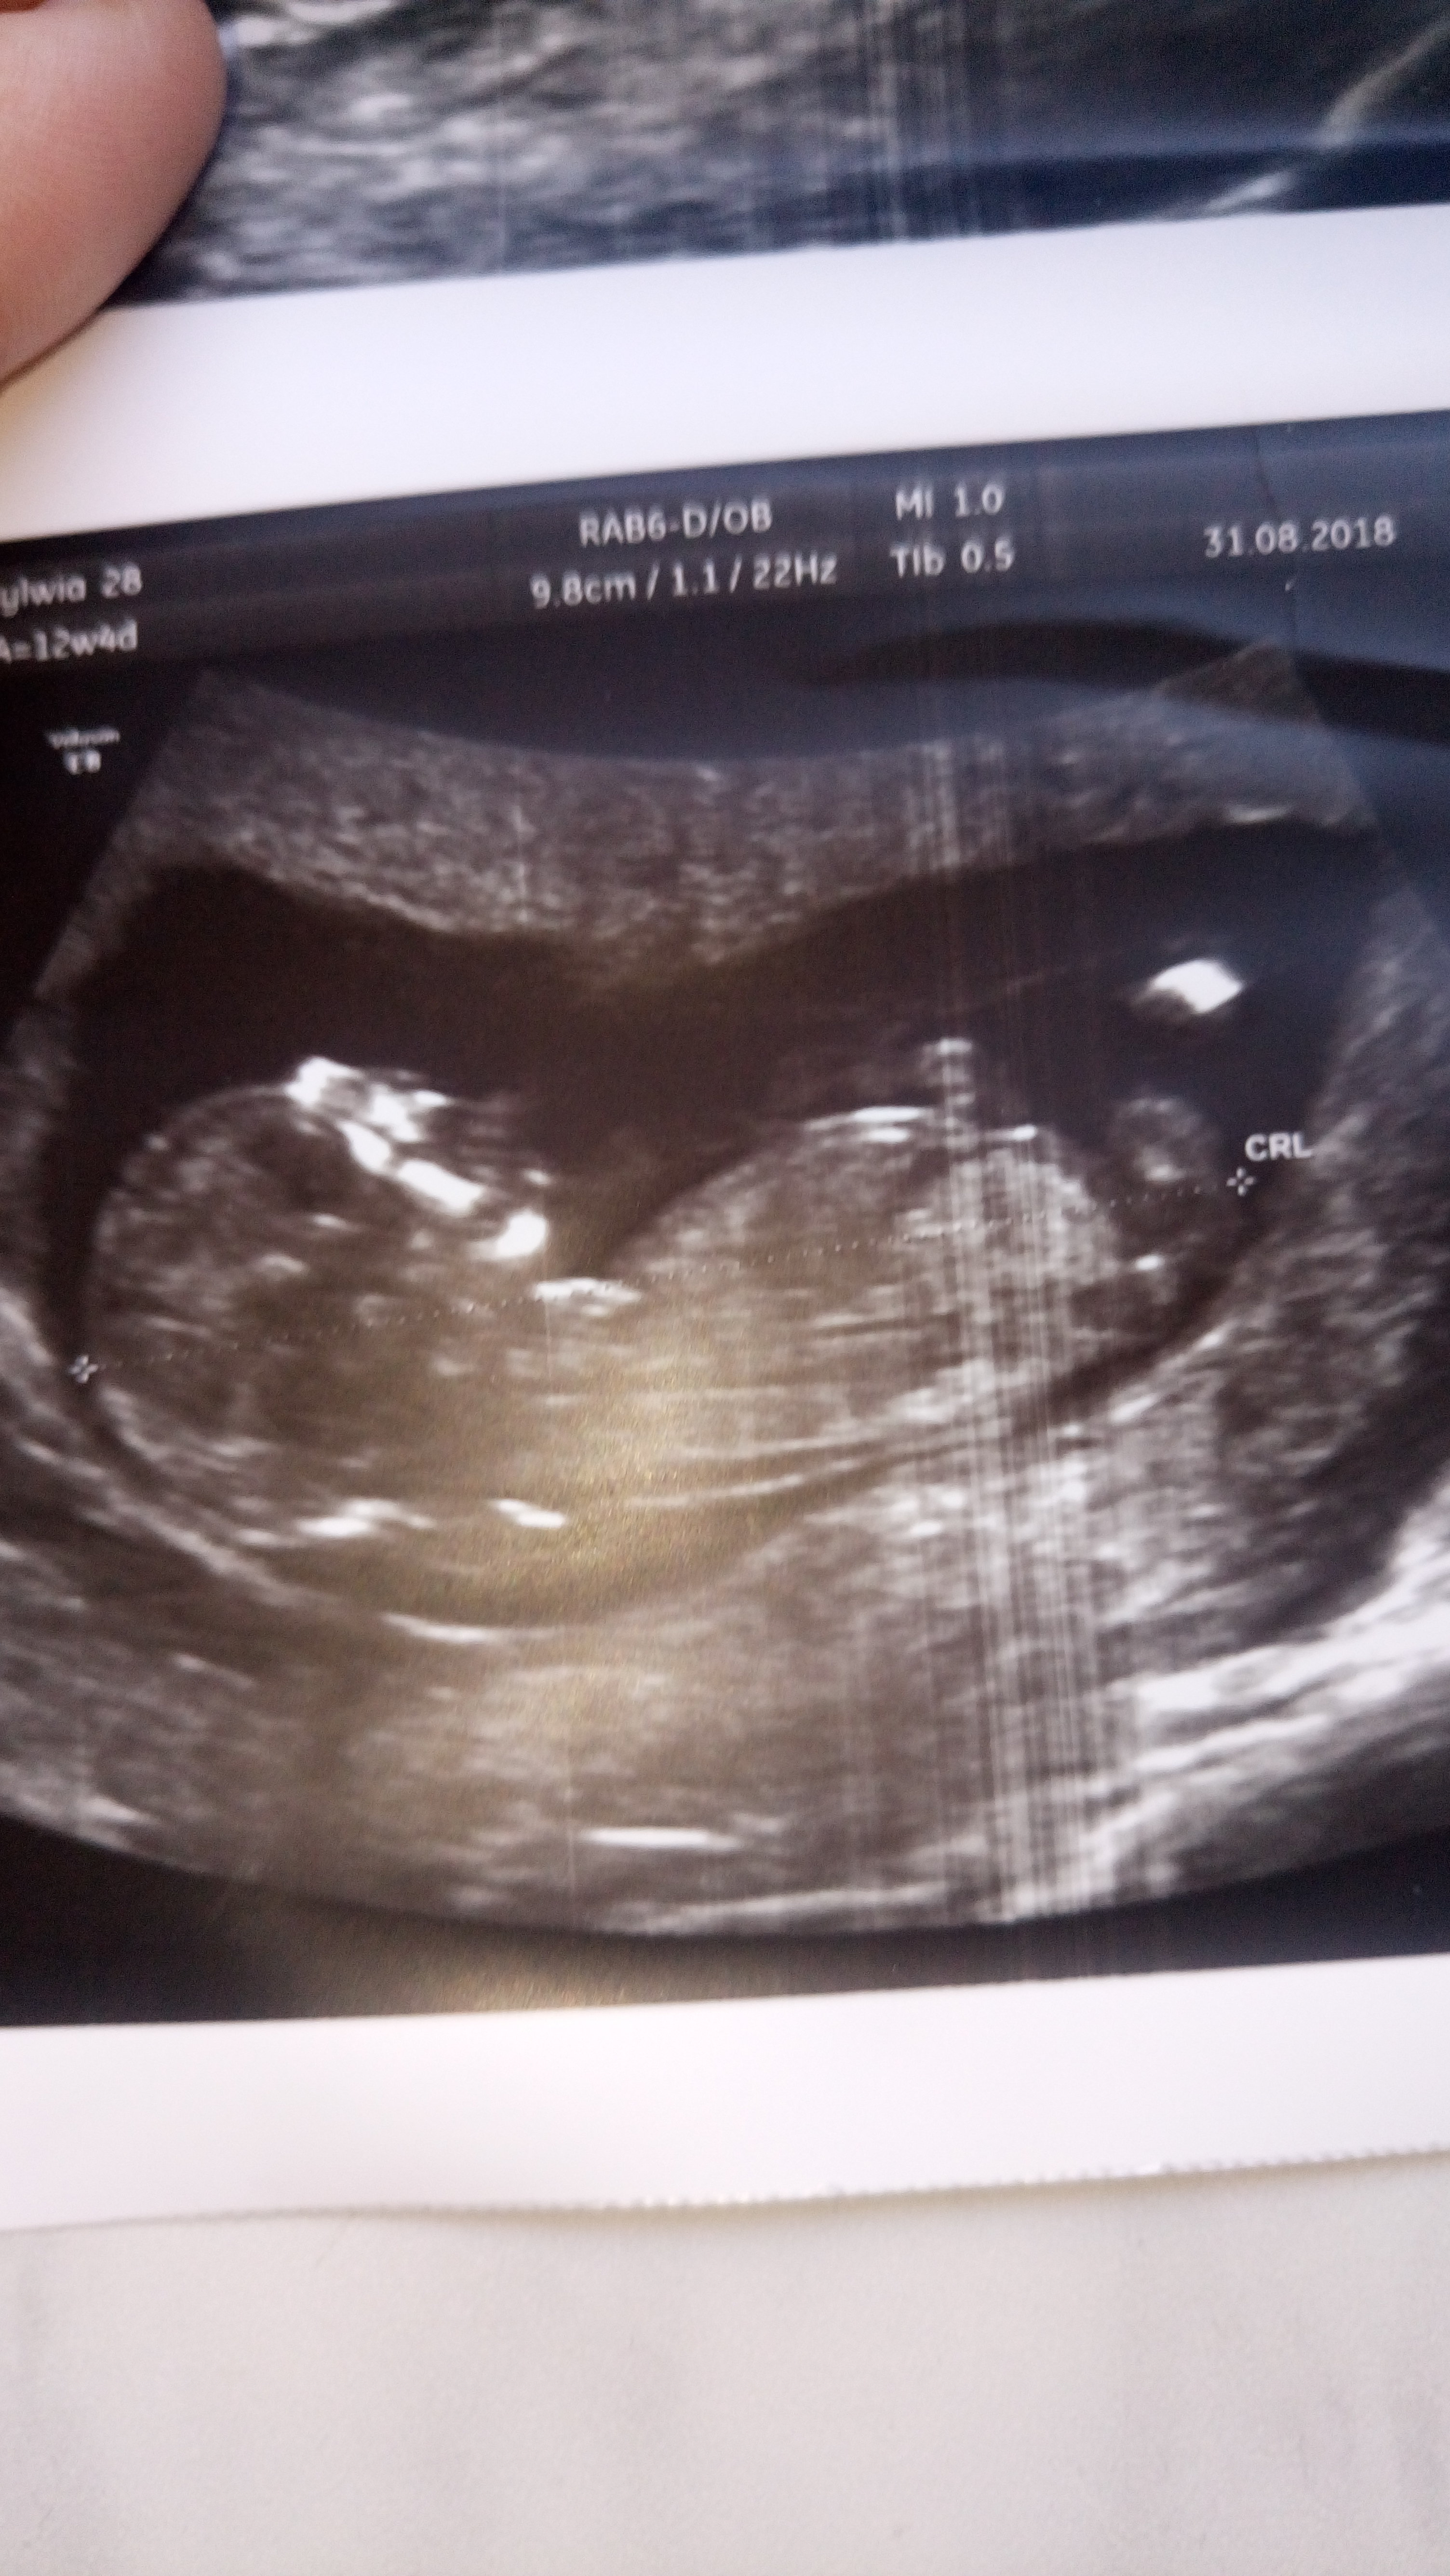

Witam w 19 tygodniu ciąży dowiedziałam się ze będę miała dziewczynkę w 20 tyg okazało się jednak , że to chłopak. Sama już nie wiem bo na jednym usg widać na pewno dziewuche a na drugim chłopca. Może to pempowina ?? Może ktoś mi pomoże rozwiązać ta zagadkę

Witam Was. Może po tych zdjęciach da się odczytać płeć dzidziusia? Dodam że jest to 12+4 tc na prenatalnych Pani dr nie była pewna zajrzała tylko między nóżki na wyrostek nie patrzyła.

Załączniki

• DSC_2504.JPG

DSC_2504.JPG

1,9 MB · Wyświetleń: 408

• DSC_2503.JPG

DSC_2503.JPG

1,9 MB · Wyświetleń: 412

• DSC_2505.JPG

DSC_2505.JPG

1,7 MB · Wyświetleń: 398